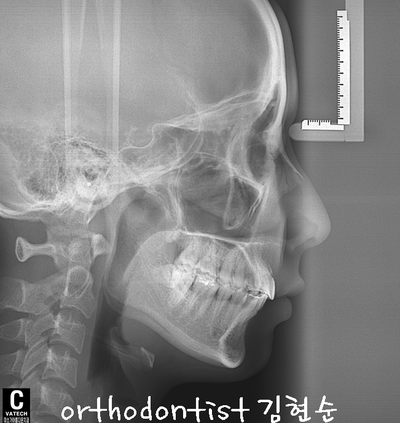

세라믹 치과 오시는 길 - 돌출 교정 - 교정 문의 환자 : 김 0 0 나이 : 24 세 F 교정 사유 : 치아 돌출 / 턱관절 호소 앞면 비대칭이 보입니다 웃을 때도 약간 삐뚤어 보입니다 입도 돌출된 모습을 확인할 수 있습니다 mi...

교정 문의 환자 : 김 0 0

나이 : 24 세 F

교정 사유 : 치아 돌출 / 턱관절 호소